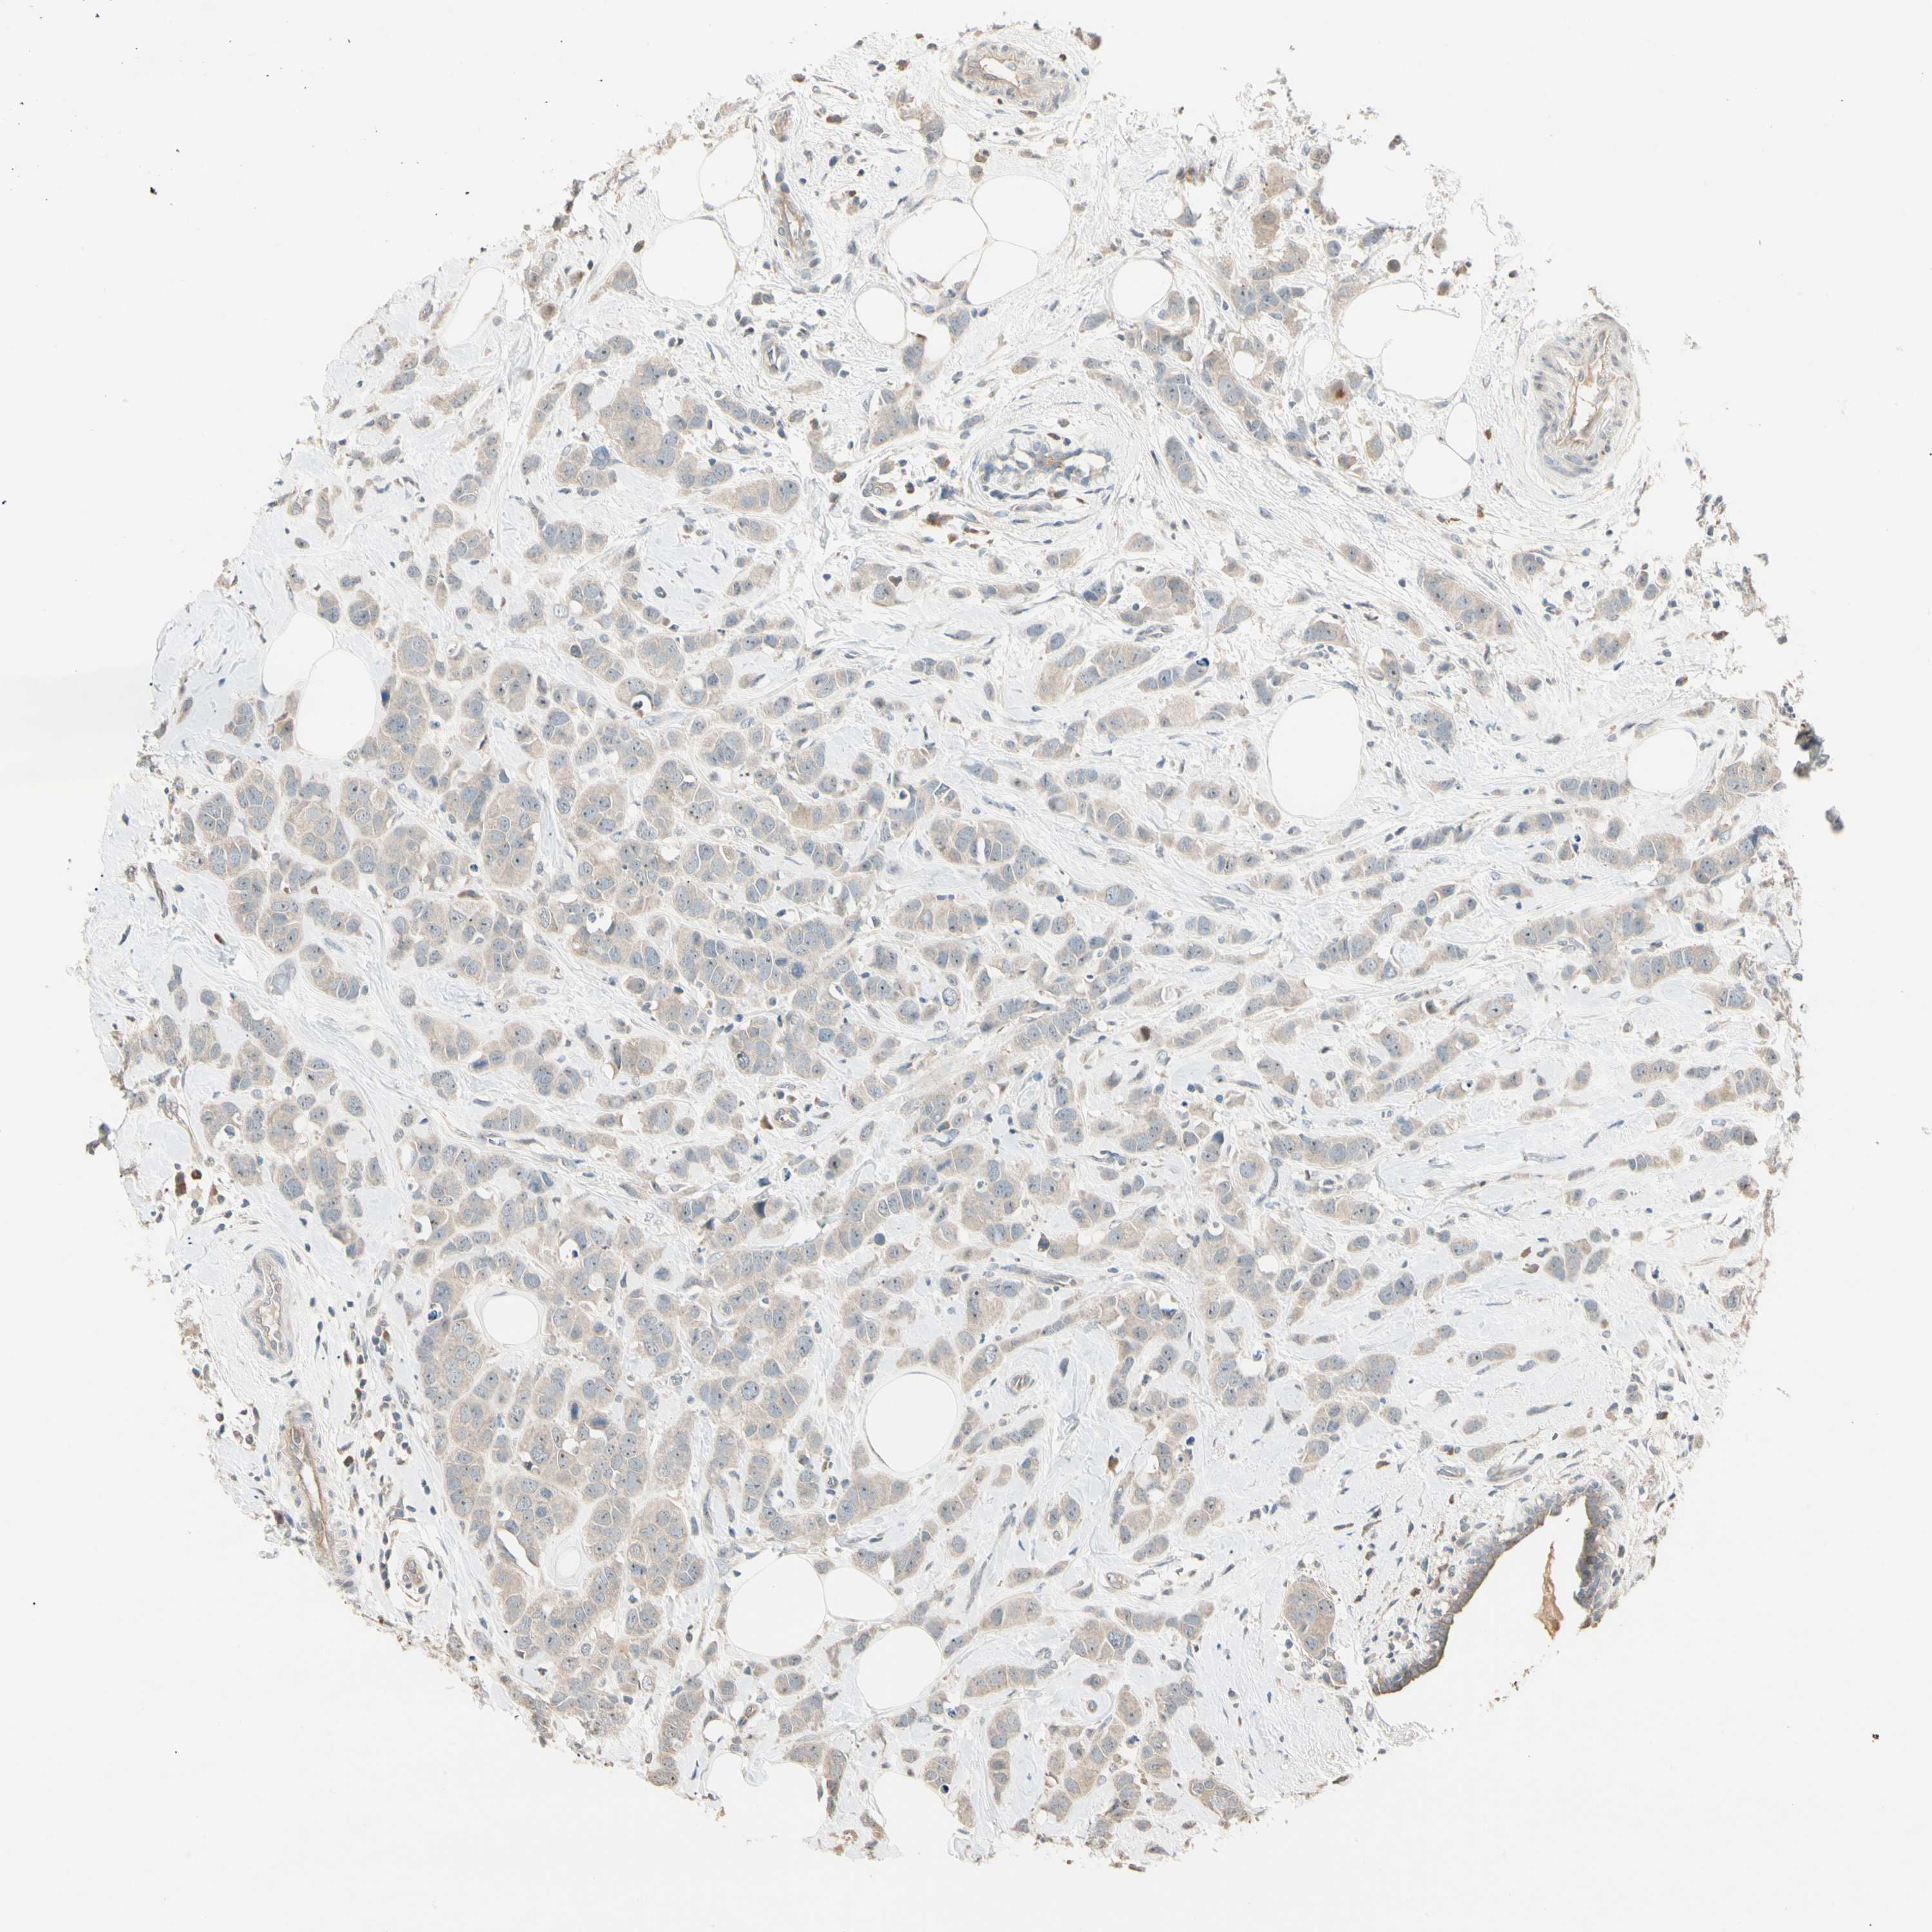

CANCER BREAST CANCER Show tissue menu

BRCA TCGA BRCA VALIDATION PROTEIN EXPRESSION

P3H2 is not prognostic in Breast Invasive Carcinoma (TCGA)